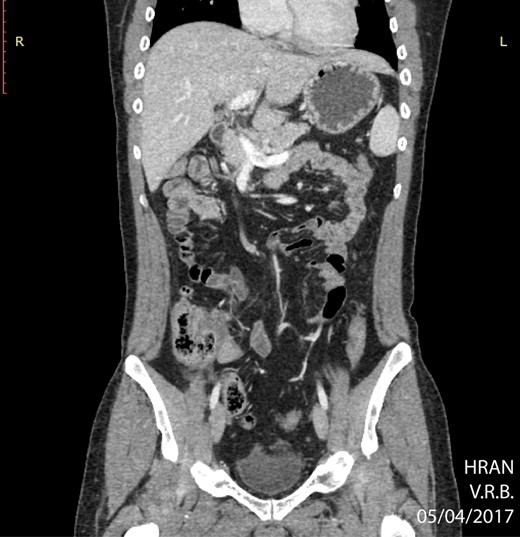

Other studies have suggested that surgery offers substantial complications and that it should not be the initial approach. A systemic review by Cirocchi et al. reported no overall survival benefit in between patients who were managed medically and those who received surgery. Moreover, it was noted that nonsurgical patients had a better outcome and concluded that chemotherapy should be the first treatment choice for patients with primary GI lymphomas. In addition, a series with 16 129 patients presenting primary GI lymphomas reported by Shannon et al. revealed that surgery did not provide greater survival benefit [8, 9]. Therefore, surgery should be reserved for cases that have an emergent character, such as and acute abdomen, like in this case. This patient had an appendectomy followed by a polychemotherapic protocol known as dose adjusted EPOCH-R. He had a complete remission in 8 months of treatment, as can be seen in Figs 1–4.

PET CT of abdomen showing regression of the abdominal mass (04/05/2017).